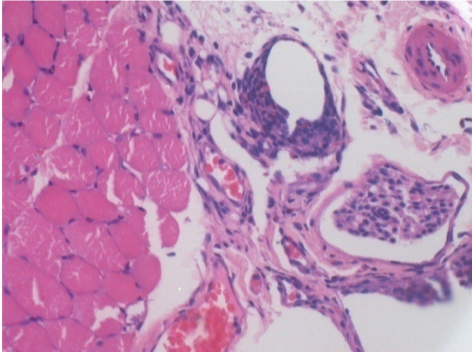

10 giorni dopo iniezione di Endopeel

Scatola Nr 2

- 10 giorni dopo iniezione 0.1ml di Endopeel nel muscolo pretibiale destro (Dx).

- Si osserva formazioni di vacuole , le quali circondate da linfociti.

- Le quali Vacuole sono differenti dal tessuto necrotico.

- La presenza di linfociti é correlata alla permeabilità delle membrane cellulari.

Sx : Controllo-100x-Giorno10

Dx:100x-Giorno10

Dx :200x-Giorno10

Dx :400x - Giorno10